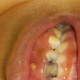

Apakah kemungkinan penyebab benjolan pada gusi atas anak perempuan berusia 5 tahun ini? Benjolan menurut orangtua muncul sudah lebih sebulan dengan ukuran menetap, seperti berisi nanah dan agak lunak saat ditekan. Anak juga mengeluh tidak sakit. Penanganan seperti apa kira kira yang tepat ya dok?

Ananda di foto megalami karies mencapai pulpa pada gigi depannya dok, dan bakteri telah menyebar hingga ke saluran akar, tulang, dan gusi, sehingga terjadi abses di gusi atas. Gigi sudah mengalami nekrosis sehingga sudah tidak terasa sakit, namun sakit mungkin timbul kembali karena infeksi di gusi dan tulang rahang.

Penanganna untuk kasus ini adalah perawatan saluran akar dan restorasi compomer crown, dan sebaiknya di rujuk ke drg spesialis kedokteran gigi anak (Sp.KGA)

Apabila tidak segera ditangani akan berefek buruk pada benih gigi tetapnya.